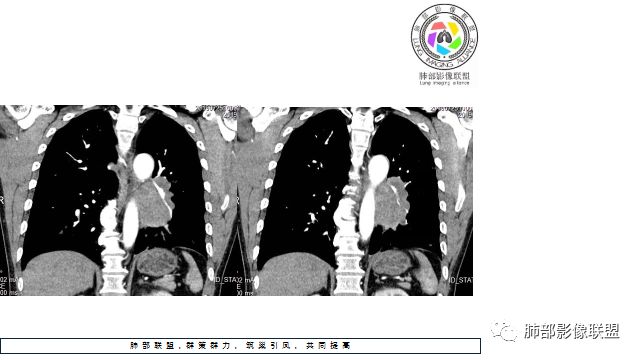

1.左下肺门区巨大肿块,支气管显示不清,轻度阻塞性炎症,没有明显肺不张,提示管腔受压狭窄可能性大于堵塞,这较少见于鳞癌。

2.病灶边缘光滑,未见明显分叶、毛刺,未见明显强化,这符合腺癌影像学特点,却符合神经内分泌癌表现。

3.病灶内密度均匀,轻到中度均匀强化,大病灶未见明显液化坏死区及空洞,不符合鳞癌而符合小细胞肺癌特点。

4.病灶内有肺动脉走形,血管局部受压,未见破坏,病灶乏血供,呈血管包埋或血管造影征;侵袭性力强及破坏力弱、血管漂浮都符合SCLC,所以鳞癌的可能性也不大。

5.左肺门块影或淋巴结肿大,竭力挤兑肺门血管结构,呈冰冻肺门;有时候SCLC可以单独呈现冰冻肺门,而没有没有冰冻纵隔。